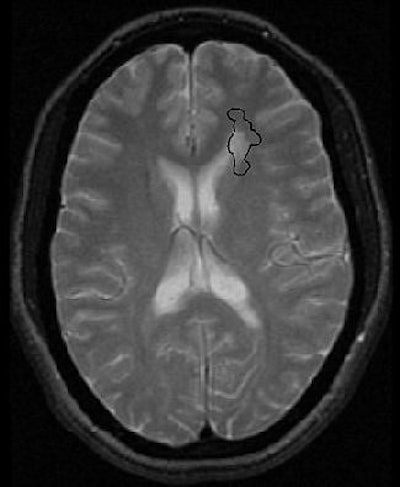

| T2-weighted images of 29-year-old woman illustrate centrifugal method of interrogating normal-appearing white matter (WM) adjacent to MS plaques. Axial T2-weighted MR image shows demyelinating plaque adjacent to anterior horn of left lateral ventricle. Kealey SM, Kim Y, Provenzale JM, "Redefinition of Multiple Sclerosis Plaque Size Using Diffusion Tensor MRI," (AJR 2004;183: 497-503). |

Diffusion tensor imaging has proven adept at assessing the microarchitecture of the brain. In addition, fractional anisotropy (FA) values -- the degree to which water molecules diffuse in one direction -- for normal-appearing white matter are lower when adjacent to MS plaques, according to a study by Dr. Susan Kealey and co-authors in the American Journal of Roentgenology. FA maps offer good gray-white matter contrast and a high contrast-to-noise ratio.

Kealey's group set out to compare the size of MS plaques with lesion size as defined by a thresholding technique on FA maps. They suggested that combining FA maps and diffusion tensor imaging would produce substantial differences in plaque size compared to conventional MR.

"Our criteria for deciding whether a lesion on T2-weighted images represented an MS plaque were that it be oval in appearance, oriented toward or abutting the lateral ventricles, and lacking associated restricted diffusion," they wrote (AJR, August 2004, Vol. 183:3, pp. 497-503).

A threshold of 40% decrease in FA was set for defining abnormal-appearing white matter on FA maps.